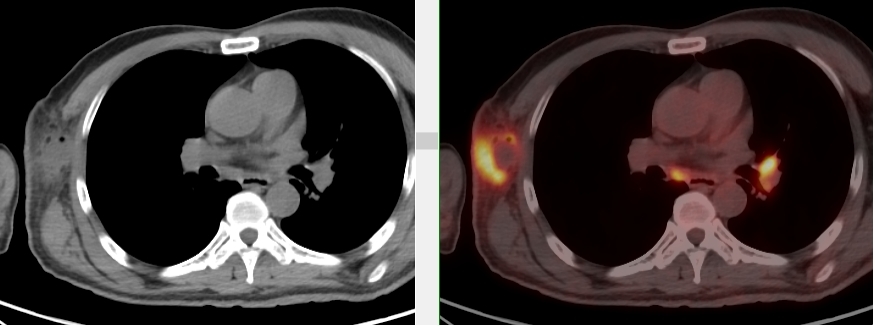

完善PET/CT檢查示:右側(cè)腋窩、雙側(cè)中下頸部、縱隔、雙側(cè)肺門多發(fā)MT,建議淋巴結(jié)活檢。后患者行右腋窩淋巴結(jié)切除活檢術(shù),經(jīng)北京大學(xué)第三醫(yī)院病理科會診示:右腋窩淋巴結(jié)惡性腫瘤,呈淋巴竇內(nèi)生長模式,瘤細(xì)胞呈上皮樣,異型性明顯,伴中性粒細(xì)胞浸潤。結(jié)合病史及免疫組化,考慮為SMARCA4(BRG1)缺失的胸部腫瘤,伴神經(jīng)內(nèi)分泌標(biāo)記表達(dá)。

本例為罕見病理類型的腫瘤,影像學(xué)表現(xiàn)無明顯特異性,診斷困難。強(qiáng)化CT和穿刺病理已基本明確為惡性腫瘤,行PET/CT檢查一是為了全身檢查,完善分期,二是根據(jù)PET代謝情況指導(dǎo)進(jìn)行生物靶區(qū)活檢,進(jìn)一步明確病理診斷。最終,PET/CT除縱隔病變外發(fā)現(xiàn)更多頸胸部淋巴結(jié)代謝異常,綜合考慮后對腋窩淋巴結(jié)進(jìn)行切除活檢,最終得到病理證實(shí)。